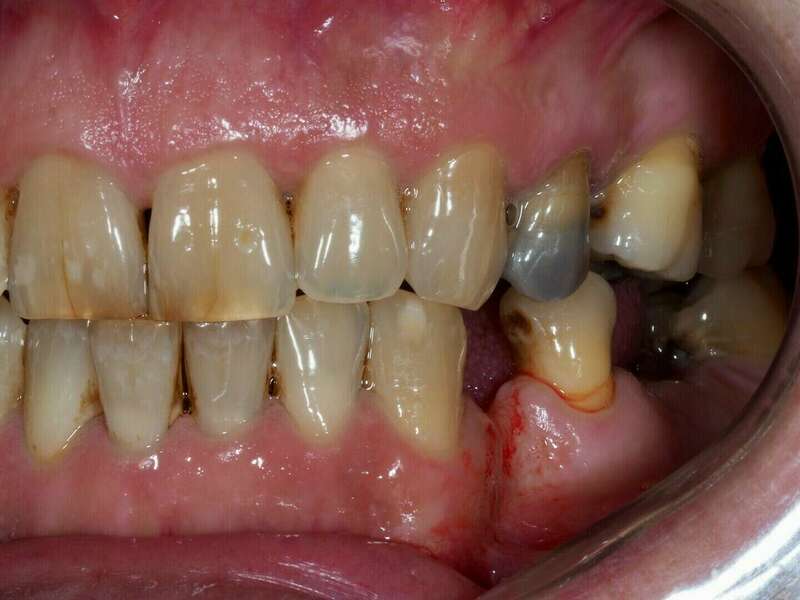

Patient venu en consultation pour une réhabilitation complète esthétique et fonctionnelle, les gênes majeurs étant les usures , les dents manquantes et la teinte de ses dent.

Avant